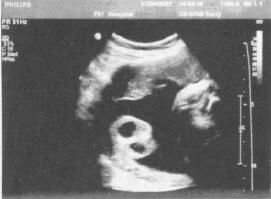

這些病症多無異常體徵。婦科檢查發現子宮體大小正常或稍大、較軟,有明顯壓痛,有時有宮頸舉痛;雙側附屬檔案檢查,輕者正常,重者可有壓痛或增厚,或捫及腫塊:後穹窿可有觸痛,甚至行後穹窿穿刺可抽出不凝固的暗紅色血液,故有異位妊娠樣綜合徵之稱。但如合併宮腔積血,查體可發現子宮增大飽滿,輕壓痛,有時可合併宮頸舉痛。B超檢查宮腔內膜線中斷,內膜菲薄,宮腔內可有液性暗區。